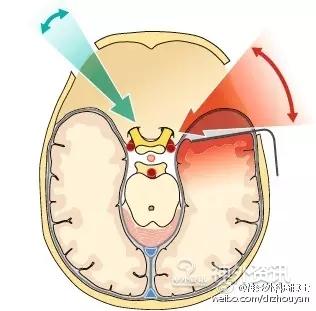

从神经外科出现开始,直至现在——开颅需要花费数小时——这是事实,多数人认为这也是天经地义的。这是因为多数神经外科医生普遍采用的仍是大范围、广泛的开颅方法。这也同时造成了另外一个事实:脑组织表面遭受非生理学环境的损伤,如空气、冲洗、贴敷材料或是脑压板的压迫力。我们需要特别注意,这些脑表面的微损伤很有可能就是术后癫痫发生的原因。这也同时解释了“为什么开颅手术的病人术后常规都要使用抗癫痫药物进行预防性治疗?”这里,我们先进行一个比较,一方是keyhole开颅方法,骨瓣直径约2cm;另一方是传统的广泛大范围开颅方法,骨瓣直径约8cm。比较的内容就是脑皮层暴露的范围和外科创伤程度。比较的方法是利用公式计算:面积=π×r2(r为骨瓣的半径)。结果是:传统的开颅方法脑表面暴露的面积是π×r2=4cm2×π=50.27cm2;keyhole开颅方法则为π×r2=1cm2×π=3.14cm2。显而易见,keyhole可以显著的减低脑皮层表面的损伤。当然,并不是所有的病例都适合,需要具体问题具体分析。

同时,keyhole开颅方法还可大大减少脑组织的牵拉。1934年,Eugene M. Landis阐述了毛细血管血压的生理范围。自此之后,大量的实验和临床研究均表明,术中过度脑牵拉一定会导致明显的脑组织损伤,并可产生永久性神经功能障碍。这个研究结果目前已获广泛认同。为了能使牵拉脑组织的程度降至最小,医生们想了很多办法,比如使用特殊的麻醉技术以降低脑组织的张力,发明特殊的脑牵拉设备,以及采用特殊手术体位等。但是,最好的牵拉技术就是“不牵拉”。仔细选择一个合适的、侵袭性小的手术入路,并使脑组织暴露和牵拉都降至最小,就可以显著降低颅内结构的损伤几率。

A. 标准的大范围开颅,暴露术野深部病变的视角呈漏斗型; B. 这种传统的大范围开颅方法可以被视为若干keyhole手术入路的整合;C. 只要选择正确的小骨窗路径,手术视角呈扇形扩大。路径越短,手术视角越窄;而路径越长(术野深部病变),手术视角则越宽。这种路径选择方法,有时还可同时处理对侧的病变。

当然,keyhole也存在很多缺点,比如手术路径必须事前设定好,术中定位定向存在一定困难。此外,由于手术器械和显微镜光线几乎共轴,所以视角较为狭窄。显微镜的光线进入到深部病变的强度不够。

问题 4:术者必须看到解剖结构,这才是最安全的。Keyhole的小骨窗不利于显微镜的光束进入到深部区域。为了解决这个问题,使用神经内镜可以有效的弥补手术显微镜的不足。